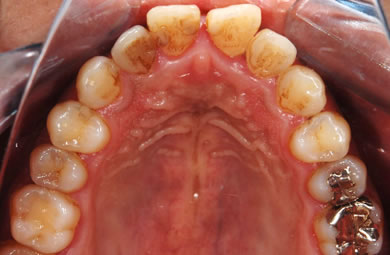

| 性別/年齢 | 男性 / 29歳 | ||||||||||||||||||||||||||||||||

| 主訴 | 歯並びを綺麗にしたい。奥歯の銀歯が目立つので白くしたい。 | ||||||||||||||||||||||||||||||||

| 治療方針 | 上の前歯部に関しては審美的回復の優先を切望されているため、透明感のあるオールセラミックのハイクオリティタイプを使用。 | ||||||||||||||||||||||||||||||||

| 治療内容 | オールセラミック(ハイクオリティ)3本、ハイブリッドセラミックインレー10本 | ||||||||||||||||||||||||||||||||

| 総治療費 | 714,286円 | ||||||||||||||||||||||||||||||||

| 治療期間 | 7ヶ月 |